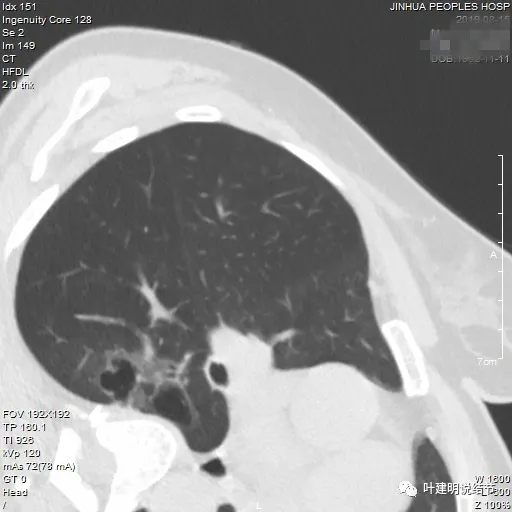

再看2024年9月时的影像:

病灶出现,紧贴叶间裂,有小血管走向病灶侧。

中间有空腔,叶裂侧实性并牵拉叶间裂。

囊腔灶、轮廓清、小血管进入囊壁、囊壁厚薄不均、叶间胸膜牵拉。

表面不平、混合密度、囊腔壁厚薄不均、内壁不光滑、有细支气管扩张通气征。

明显壁厚薄不均的囊腔灶,囊壁基本实性,表面不平,内壁不光滑,且邻近叶间裂并牵拉叶裂。

表面毛糙不平,部分区域有点像锯齿状。

表面不平细毛刺,中间空腔欠光滑、囊壁厚薄不均。

上图囊壁较厚,密度较高,轮廓与边界较清。

病灶边上也有多发小空泡样征,说明病灶有收缩力或对周围结构有影响。

上图显得像混合密度伴偏心空腔征。

上图是病灶边缘部位有血管走向病灶侧,并达病灶的地方有异常增粗。